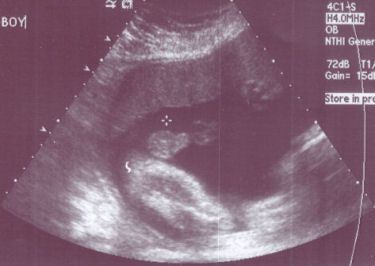

عکس جنین پسر در سونوگرافی هفته بیستم و سوم بارداری

آلت تناسلی پسر بطور واضح در بین پاهای او مشخص در هفته بیست و سوم بارداری می باشد. در هفته بیست و سوم شما 5 ماهه باردار هستید. جنین شما حدود 501 گرم وزن دارد و قدش 28.9 سانتی متر است. او حالا به اندازه یک گریپ فروت است.